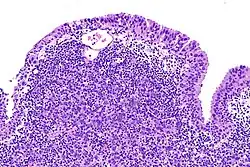

Rak urotelialny pęcherza moczowego

Inwazyjny (naciekający) rak urotelialny jest definiowany jako obecność inwazji nowotworowej poniżej błony podstawnej urotelium[74]. Makroskopowo inwazyjne nowotwory urotelialne mogą przyjmować formę brodawkowatą, polipowatą, guzkową, litą, tworzyć rozlany naciek ściany pęcherza moczowego. Zmiany mogą występować pojedynczo lub wieloogniskowo[75]. Typowo większość guzów pT1 jest brodawczakowata o niskim lub wysokim stopniu złośliwości histologicznej, z kolei guzy o większym zaawansowaniu pT2–T4 wykazują morfologię niebrodawczakowatą i cechują się wysokim stopniem złośliwości[76][77].